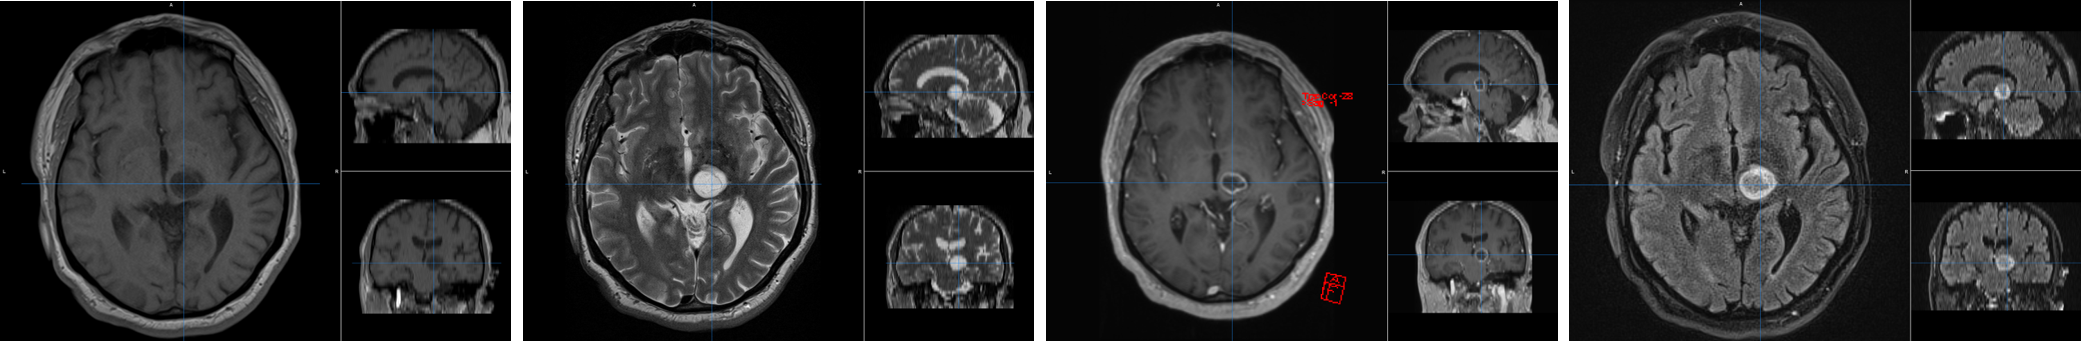

In Belgium, 800 people are diagnosed with a primary brain tumour each year. Their life expectancy depends strongly on the tumour type and molecular characteristics, and ranges from several decades for low-grade tumours to only about one year for the most malignant types. An accurate diagnosis and prediction of genetic markers is therefore of primary importance. In this project, we will implement a method for automated, non-invase brain tumour characterisation based on pre-therapy MRI, using Convolutional Neural Networks.